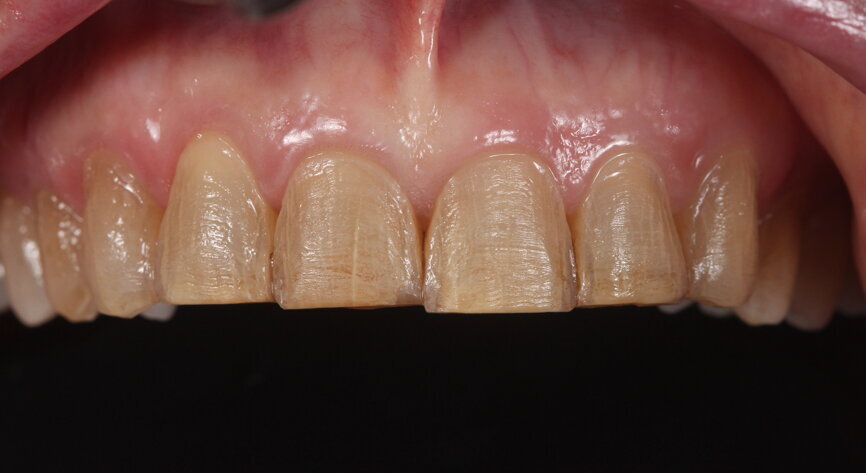

Fig. 12: Preoperative smile photograph.

Fig. 13: Preoperative intra-oral photograph.

A 62-year-old woman presented to the Comprehensive Care Clinic at the Dental College of Georgia at Augusta University, Augusta, Georgia, US, with the chief complaint of worn and stained anterior teeth (Figs. 12 & 13). The patient was a smoker and reportedly smoked a pack per week.